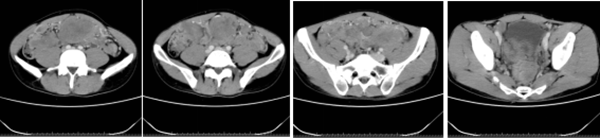

在予以了6个周期高强度的化疗后,复查CT提示腹腔其余病灶较前缩小,但左侧髂血管旁病变较前增大。为进一步控制肿瘤,予以了全腹腔适型调强放疗,放疗1月后复查CT见腹盆腔内多发结节及肿块灶较前缩小,肝包膜多发结节较前稍缩小。

2021年2月,再次复查CT示腹盆腔内多发结节较前进一步缩小,得知此消息后,小李的脸上总算出现了久违的笑容。